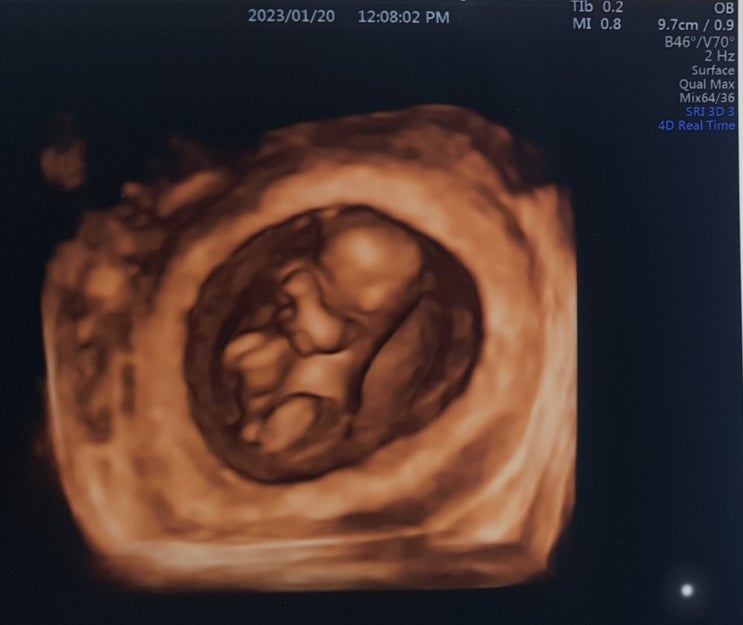

[엽상종/섬유선종] 초음파, 조직검사 엽상종 진단 후 첫 번째 추적검사, 그리고 임신, 모유수유

2022년 초 멍울이 있는 것을 알게 되고 (코로나로 인해 한국에 못 와서 병원 못 가다가) 2022년 7월 여성병...